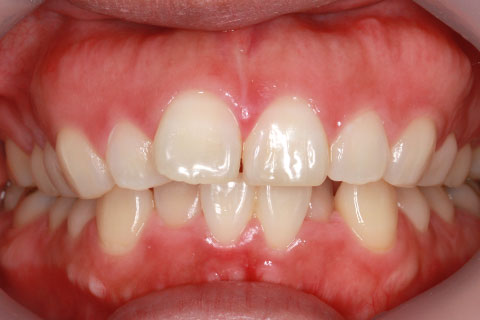

ハーフリンガル矯正3:上の歯のみ舌側矯正で治療(矯正期間24ヶ月)

治療前

- 年齢・性別

- 25歳女性

- 治療期間

- 2年0ヶ月

- 抜歯

- 上下4番抜歯

- 治療費

- 110万円

- 治療内容

- 施術の副作用(リスク)

- 表側矯正と比較して、力学的な操作性が複雑なため、ボーイングエフェクトを起こしやすい。